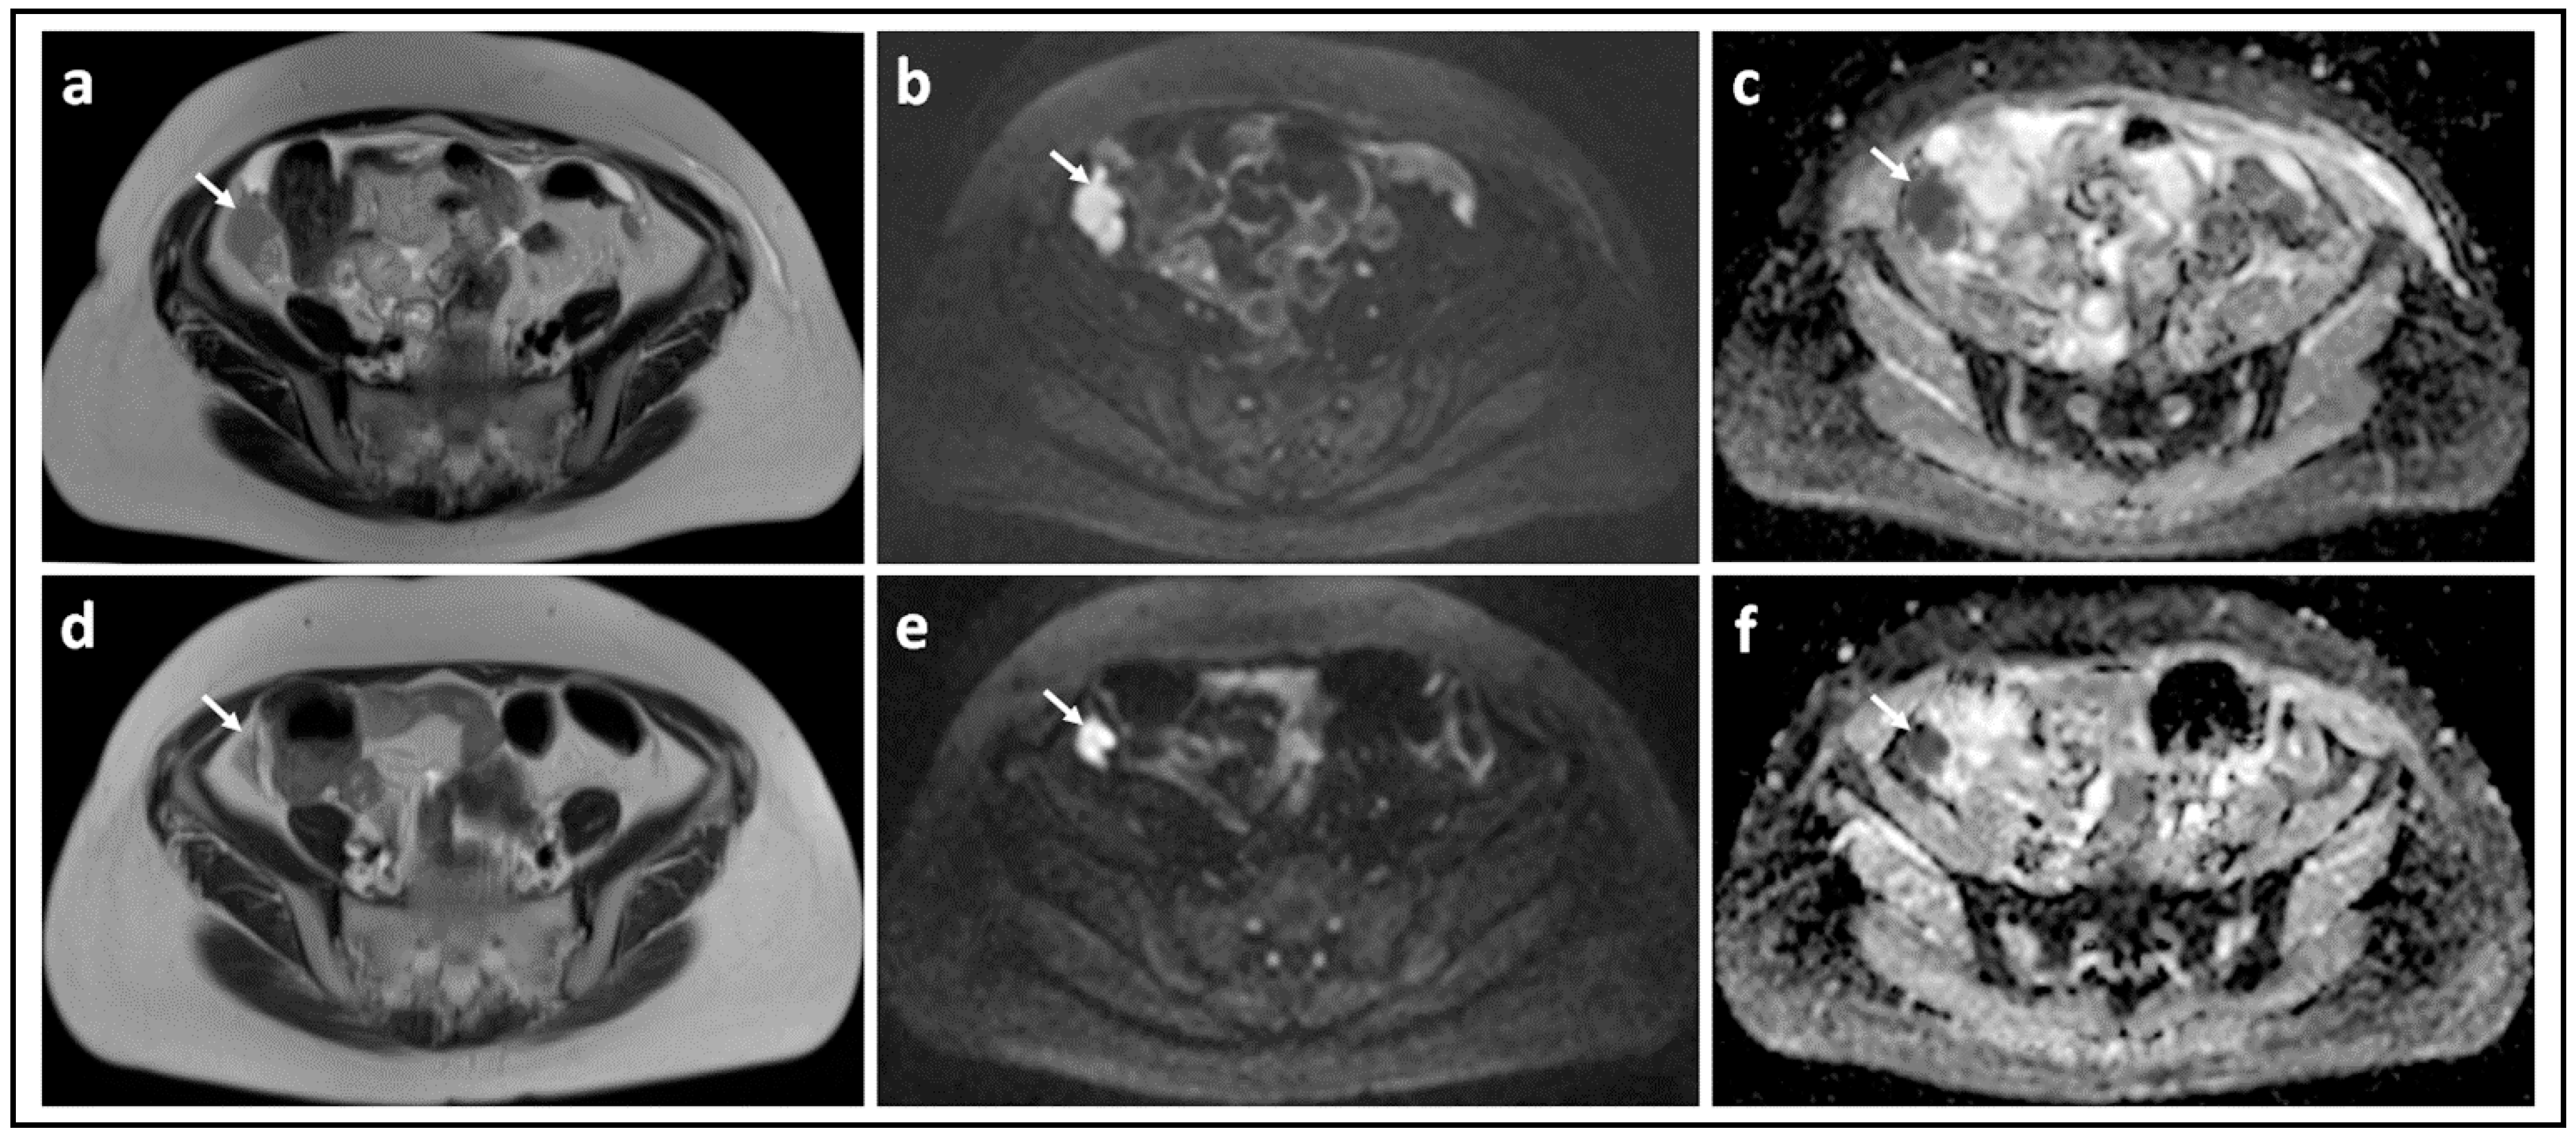

Figure 1.

Peritoneal metastases in high grade serous ovarian cancer showing increasing lesion conspicuity with increasing b-value: T2-W (a) and DW-MRI at b-values of 0 s/mm2 (b), 100 s/mm2 (c), 500 s/mm2 (d), and 900 s/mm2 (e). The irregular metastatic deposits on the surface of the bowel and in the mesentery (arrows) show diffusion restriction. They increase in conspicuity and contrast as diffusion weighting increases because they retain signal while signal from adjacent normal tissues diffuses away.